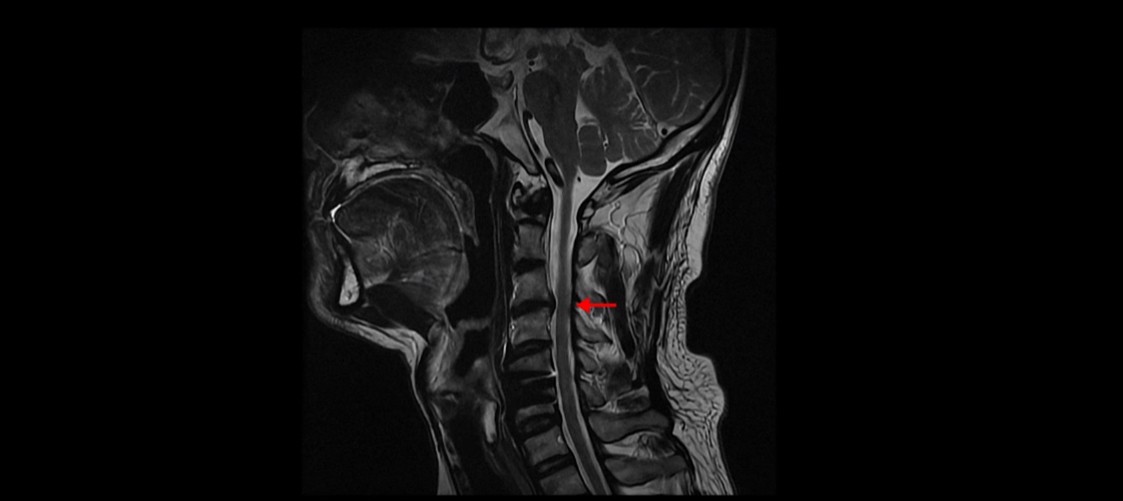

먼저 이분 MRI를 보면서 상태를 설명해 드린 후 어떻게 이런 환자들이 근육재활치료로 좋아질 수 있는지, 얼마 만에 좋아질 수 있는지, 치료는 어떻게 하는지 자세히 설명 드리겠습니다.

저희 모커리한방병원에서는 목이든 허리든 수술이 잘 됐다는 데도 계속 아프다면 당연히 근육 문제를 의심하고 치료해야 한다고 그렇게 반복해서 설명하는데도 신경 주사만 맞거나 아니면 치료를 포기하거나 아니면 추가적인 수술을 받는 분들도 있습니다. 이 환자분도 보시다시피 목의 다른 마디에도 퇴행성디스크와 협착이 있습니다.

이 환자분의 증상인 목, 어깨, 등 통증, 두통, 어지럼증, 눈 불편함, 시력 저하 이런 증상들은 원래가 목 근육 문제와 매우 밀접하게 관련된 증상들입니다. 저희가 목디스크, 목협착 환자의 99%는 거북목 환자라고 말씀드렸습니다. 이런 증상들은 거북목과 매우 밀접한 관련이 있습니다.

목디스크의 제일 중요한 증상은 한쪽 손과 팔, 어깨 특히 견갑골 쪽 통증과 저림 증상입니다. 앞서 말씀 드린 그 외의 여러 증상들은 목 근육 문제와 매우 밀접한 관련이 있습니다. 그래서 목디스크 수술 후 한쪽 손, 팔, 어깨 저림 증상이 없어졌다고 해도 이런 다른 여러 복합 증상들은 좋아지지 않을 수도 있고 또 목 근육 문제로 인한 이런 여러 증상들을 목디스크 증상으로 오진했을 수도 있습니다.